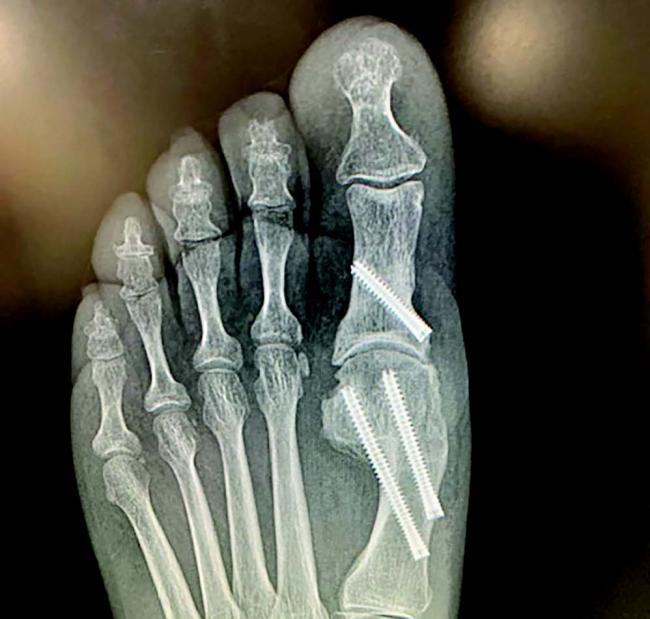

Hypermobility and Hallux Valgus: Where MIS Fits

Panelists debated the management of first ray hypermobility in the context of bunion correction. Traditional approaches often lean toward first TMTJ fusion, they noted, especially when instability is suspected. However, the panel emphasized:

- Transverse Plane Stability as a critical factor in recurrence risk. MIS approaches can realign the mechanical axis and offer stabilization benefits without requiring TMTJ fusion in all cases.

- Selective Use of Fusion: While MIS can restore stability for many, fusion remains a valuable option when significant hypermobility is evident or conservative MIS correction fails.